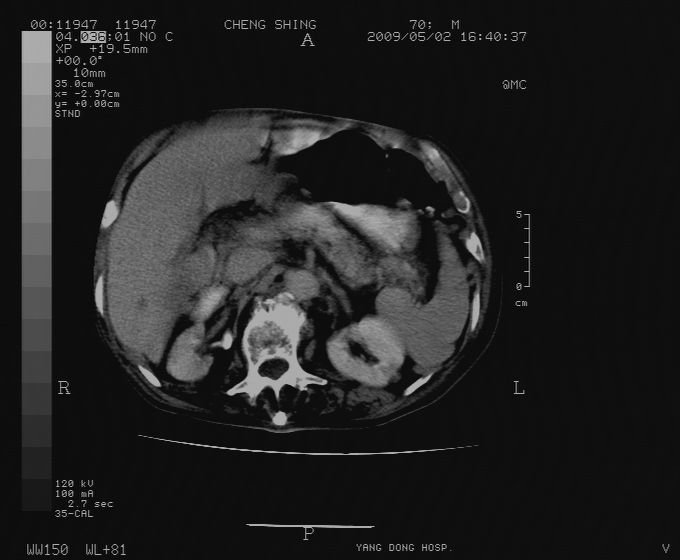

标题: CT19743:男70岁,肺部疾病入院,B超发现肝右叶占位,CT [打印本页]

标题: CT19743:男70岁,肺部疾病入院,B超发现肝右叶占位,CT

肝表面塌陷,病灶周围有子灶,前面较大子灶强化符合肝癌表现,考虑肝癌肝转移可能性大.

1.考虑肝癌肝转移

2.两侧胸水,左下肺不张!

1)考虑肝癌并肝内转移。2)少量腹水。3)双侧胸腔积液。

1)考虑肝癌并肝内转移。2)少量腹水及双侧胸腔积液。3)椎体退变。